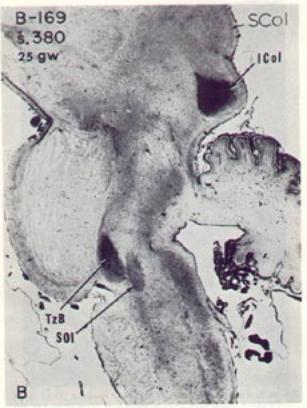

Early myelination of the human brainstem

auditory pathway, at 25 gestational weeks

(above, sagital view) and 29 gestational weeks

(right, horizontal view).